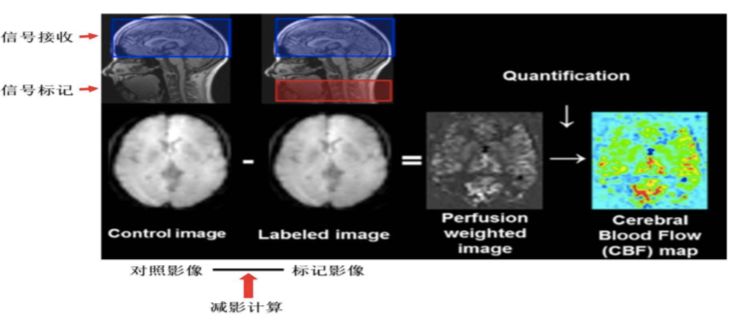

脑灌注[s0]脑灌注与认知功能障碍(脑灌注概念)[s1]ct脑灌注原理及临床应用[s2]脑灌注是什么意思 来自搜狐网[s3]脑灌注[s4]PPT 注释 | 脑灌注成像(DSC)的临床应用(1)--李润涛[s5]脑灌注:xe-ct评价脑血流量指导扩容 2.5 xe-ct de the decision to p[s6]脑灌注是怎么做的,是多个序列,根据序列时间分析血流?#码农的日常# 多个心脏序列的连续渲染就是跳动效果[s7]文献编译| 儿童烟雾病脑灌注成像 磁共振asl与pet比较[s8]图片[s9]PPT 注释 | 脑灌注成像(DSC)的临床应用(1)--李润涛[s10]Image[s11]关于什么是ct脑灌注成像?你一定要知道这些知识![s12]基于动脉自旋标记技术的帕金森病伴抑郁患者脑灌注研究[s13]神经影像| 无需注射造影剂的脑灌注成像:磁共振asl技术进展及应用[s14]渭南市第二医院医学影像科颅脑cta脑灌注ctp(一站式成像新突破)[s15]【请您关注】总院云影像中心顺利开展ct脑灌注成像检查[s16]asl脑部灌注的原理及临床应用[s17]Image[s18]文献编译| 儿童烟雾病脑灌注成像 磁共振asl与pet比较[s19]Image[s20]ppt+注释 | 脑灌注成像(dsc)的临床应用(1)--李润涛[s21]渭南市第二医院医学影像科颅脑cta脑灌注ctp(一站式成像新突破)[s22]软件试用| 无创脑灌注定量成像3d-asl后处理[s23]脑灌注(ctp):提示左侧额颞顶部大面积灌注不足.[s24]脑灌注成像检查,您了解多少?[s25]图片[s26]核磁脑灌注图显示右侧枕顶颞缺血[s27]图片[s28]脑灌注是什么意思 个人图书馆[s29]神经影像| 脑灌注成像磁共振asl技术基本原理及临床应用(一)[s30]「夜班不求人」解读ct脑灌注[s31]图片3.jpg[s32]烟雾病患者ct全脑灌注成像及cta检查影像学特征及临床应用[s33]脑灌注是什么意思 头条[s34]PPT 注释 | 脑灌注成像(DSC)的临床应用(1)--李润涛[s35]ppt+注释 | 脑灌注成像(dsc)的临床应用(1)--李润涛[s36]2. 灌注压的稳态。合理的脑灌注压,是stbi患者术后恢复的重要干预指标,脑[s37]图2: 同侧和对侧脑灌注都有改善.自己的一点体会:我们在临床中经常碰到,[s38]ppt+注释 | 脑灌注成像(dsc)的临床应用(1)--李润涛[s39]